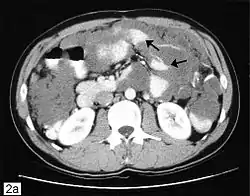

![]() تصوير مقطعي محوسب يُظهر ورم مخاطي صفاقي كاذب مع كتل صفاقية متعددة. تصوير مقطعي محوسب يُظهر ورم مخاطي صفاقي كاذب مع كتل صفاقية متعددة. | |